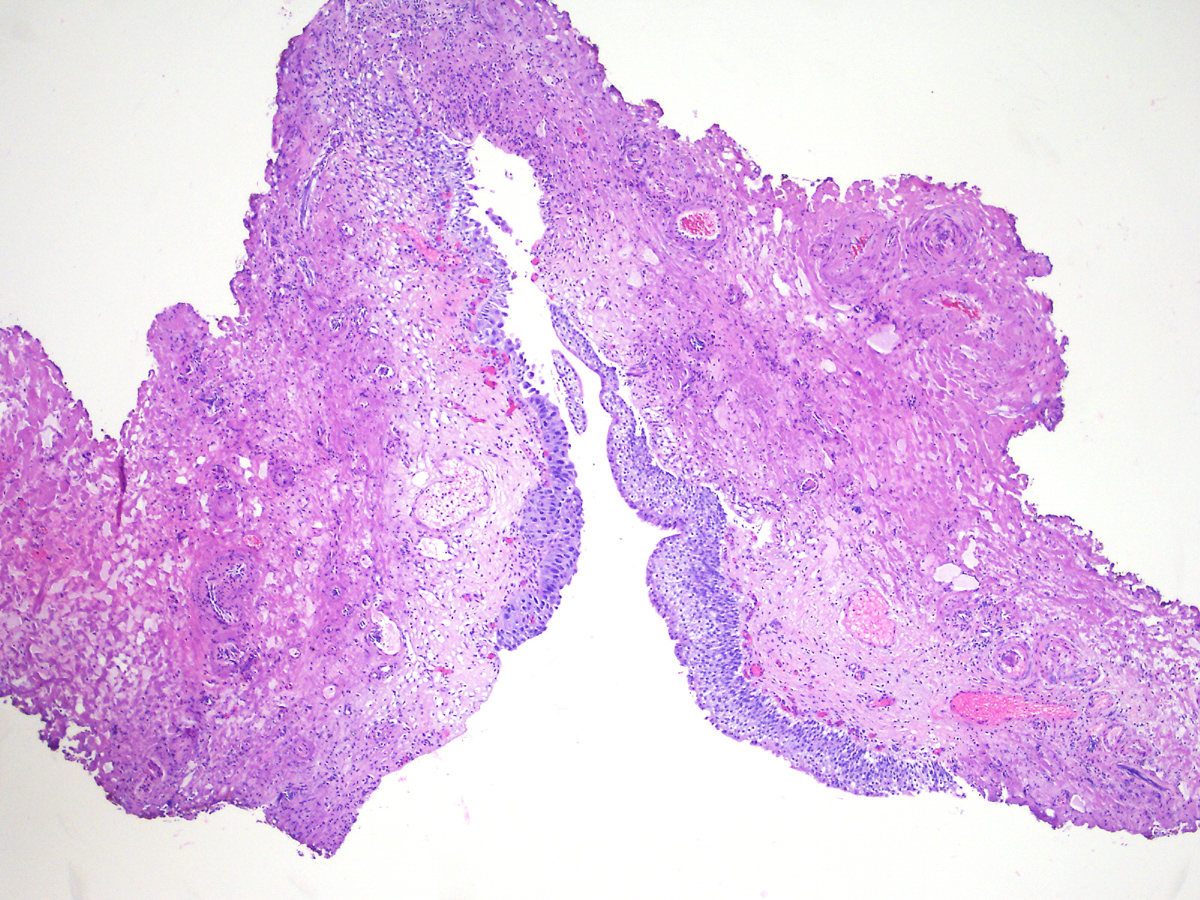

Consensus grade: Carcinoma in situ (CIS)

A 60-year-old man had atypical urothelial cells on urine cytology. Cystoscopy revealed several lesions in the bladder that were biopsied. He had a history of bladder urothelial CIS treated with intravesical BCG therapy and 3-month follow-up cystoscopies and cytologies were unremarkable.